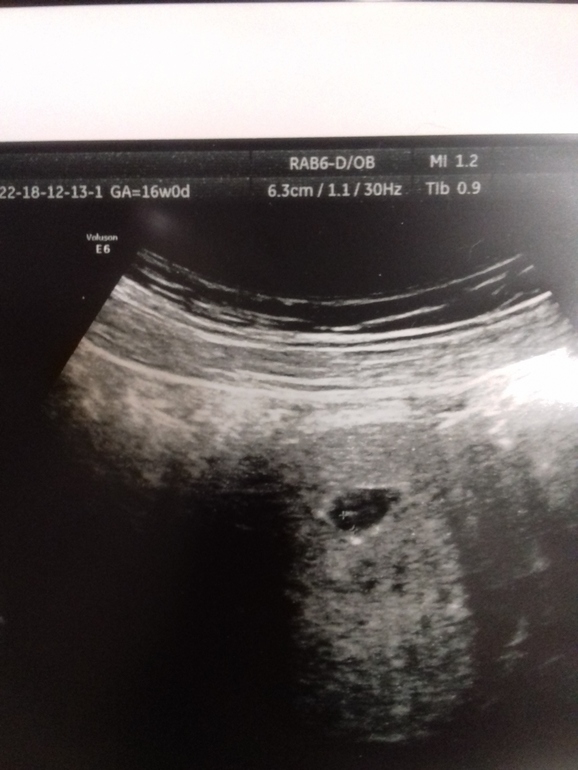

У меня в 5 нед ПЯ было всего 6,5 мм, а у вас 9 уже, не понимаю, почему они такой срок поставили. Сходите через недели 1,5, чтобы проверить сердцебиение и эмбриончик. По хгч срок беременности и размер пя ставить неправильно, так как все индивидуально.

По сроку все хорошо, на таком сроке эмбрион видят и слышат лишь хорошие аппараты. Для большинства это маленький срок. Вот правильно пишут через 7-10 дней уже все аппараты и увидят и услышат. А вот что за УЗ признаки выкидыша??? В диагнозе, что это такое?